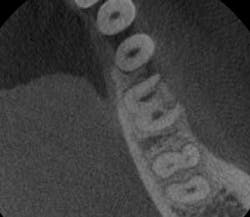

- In Figure 8, the lesion is advanced significantly (one-and-a-half years had gone by) the irregular borders and moth-eaten appearance is easily observed.

- Definitive diagnosis: external resorption.